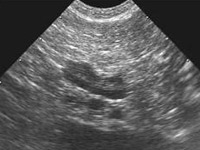

(pancreas=膵臓が腫大している)

膵炎の診断には、臨床症状、血液検査、超音波検査が必要です。血液検査では、白血球数、CRP(犬の炎症反応の指標)、肝酵素、膵酵素(アミラーゼ・リパーゼ)を測定します。アミラーゼ・リパーゼは犬の膵炎の50~60%で上昇が認められますので、スクリーニング検査には有用です。

超音波検査では、腫大した膵臓と膵臓周囲の腸間膜の輝度亢進、膵管の

拡張、腹水など診断に有用な所見が得られます。報告では、犬の急性膵炎の68%で超音波検査の異常があると示されています。